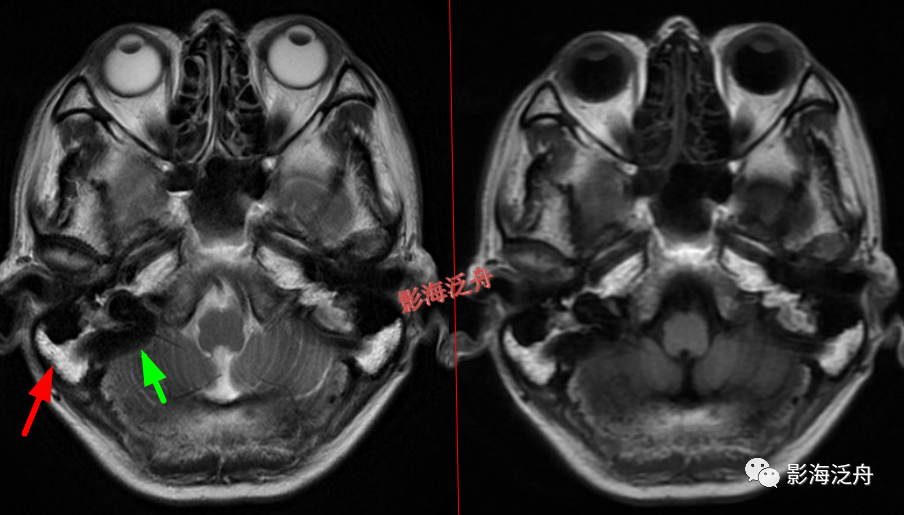

脑膜炎

患者,桥前池内可见异常增多的血管影(红箭),正常人的桥前池因为脑脊液流动产生的伪影也可以看到池内絮状低信号(绿箭),但不如右侧患者的明显,这个观察起来比较困难,就如在腹部CT

上观察患者是否存在肝脏肿大一样,需要一个经验积累的过程。黄

箭指基底动脉,蓝箭指三叉神经。